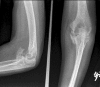

Elbow motion is essential for upper extremity function to position the hand in space. Unfortunately, the elbow joint is prone to stiffness following a multitude of traumatic and atraumatic etiologies. Elbow stiffness can be diagnosed with a complete history and physical exam, supplemented with appropriate imaging studies. The stiff elbow is challenging to treat, and thus, its prevention is of paramount importance. When this approach fails, non-operative followed by operative treatment modalities should be pursued. Upon initial presentation in those who have minimal contractures of 6-month duration or less, static and dynamic splinting, serial casting, continuous passive motion, occupational/physical therapy, and manipulation are non-operative treatment modalities that may be attempted. A stiff elbow that is refractory to non-operative management can be treated surgically, either arthroscopically or open, to eliminate soft tissue or bony blocks to motion. In the future, efforts to prevent and treat elbow stiffness may target the basic science mechanisms involved. Our purpose was to review the etiologies, classification, evaluation, prevention, operative, and non-operative treatment of the stiff elbow.